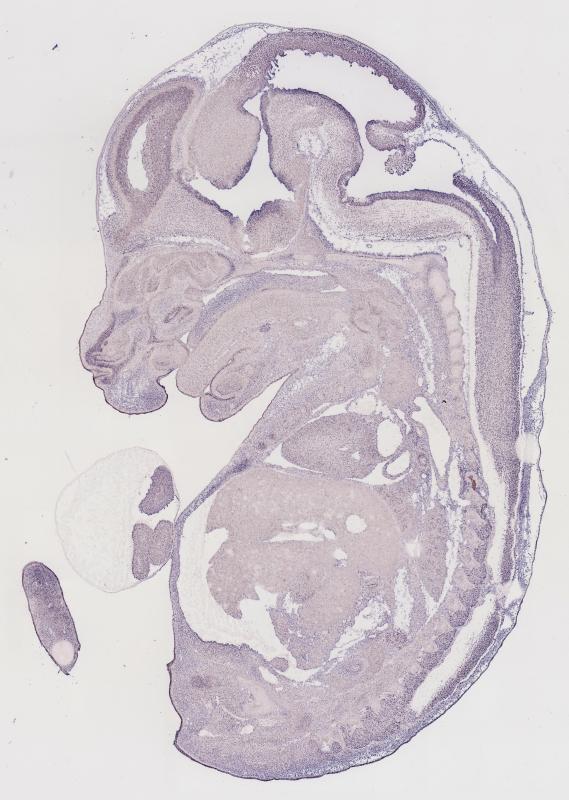

Specimen

MH837; Specimen C1251:

embryonic day 14.5